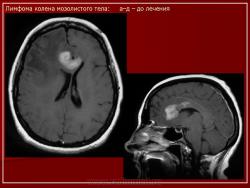

Лимфомы головного мозга.